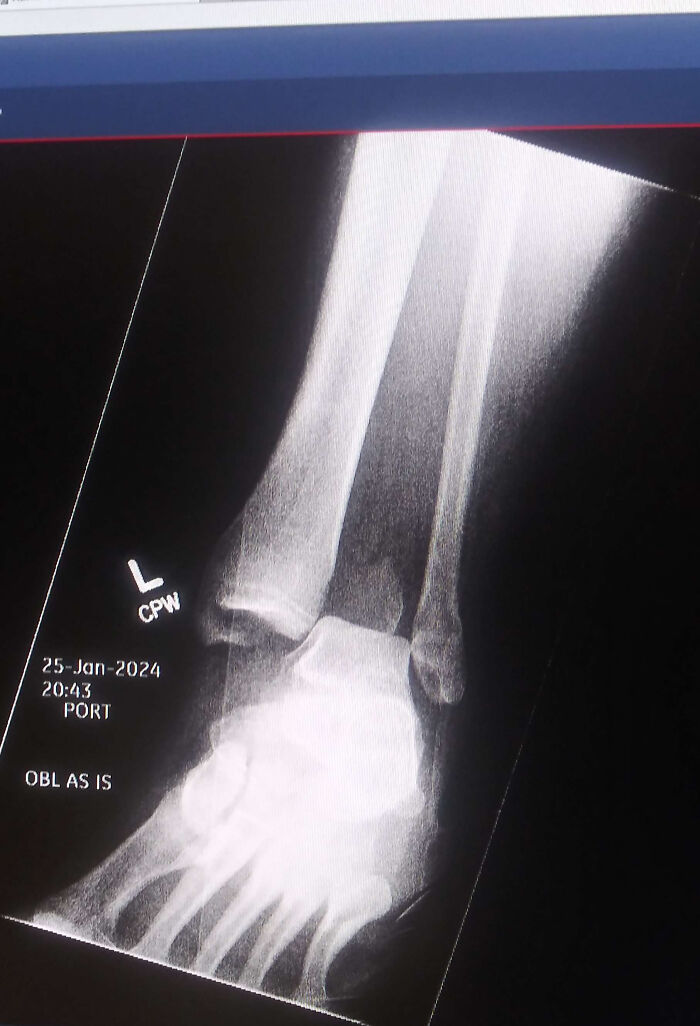

#44 Messed Up My Ankle Real Bad, Was Told To Post Here. Feel Free To Study This Or Whatever

Image credits: InquisitorDomina